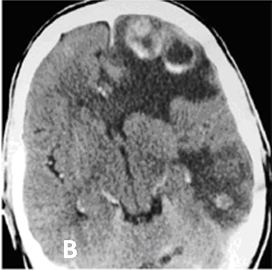

Hình 2. Hình ảnh di căn não đa ổ có chảy máu trong u trên phim CT trước tiêm thuốc của bệnh nhân ung thư phổi không phải tế bào nhỏ